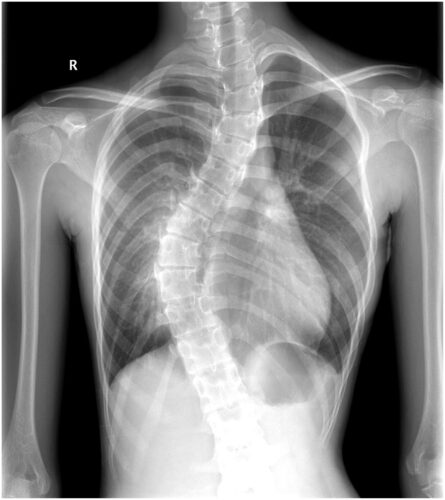

يُعد اعوجاج العمود الفقري من الحالات التي لا تقتصر آثارها على الظهر فقط، بل تمتد لتشمل مناطق أخرى من الجسم، وأهمها الحوض، الذي يُعتبر قاعدة العمود الفقري ونقطة توازن الجسم. كثير من المرضى أو الأهالي يلاحظون أن الحوض يبدو مائلًا أو غير متوازن عند المراهقين المصابين بانحناء في العمود الفقري، ما يثير تساؤلات حول سبب ذلك، وكيف يمكن تصحيحه.

الحوض هو الأساس الذي يستند عليه العمود الفقري. وعندما يحدث انحناء جانبي في العمود الفقري، تميل الفقرات إلى أحد الجانبين، فيؤثر ذلك مباشرة على توازن الحوض.

عادةً، يميل الحوض في اتجاه الانحناء، فيصبح أحد الجانبين أعلى من الآخر، فيما يُعرف بـ ميل الحوض (Pelvic Tilt) أو عدم اتزان الحوض. هذا الميل قد يسبب اختلافًا في طول الساقين الظاهري، وألمًا في أسفل الظهر أو الورك، ويؤثر على طريقة المشي والوقوف.

تشير دراسات منشورة في European Spine Journal إلى أن أكثر من 70٪ من المراهقين المصابين باعوجاج العمود الفقري لديهم درجة من ميل الحوض، وتزداد شدته بزيادة زاوية الانحناء (زاوية كوب).